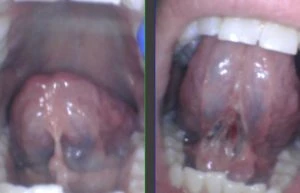

The baby below was cut into the body of the tongue (see the white area above the string), and we released it properly and saw a great improvement in symptoms. The restrictive lip-tie was also not seen, or not deemed to be a problem.

This baby was clipped at the hospital by the pediatrician and her salivary gland openings were turned into a cluster of grape-like openings because the provider clipped right through them and missed the string. Here’s the proper release on that same patient after we used the CO2 laser. Notice the better elevation of the tongue.

We see adults (like the one below) who have been clipped as a baby and still have a very tight attachment limiting their mobility and function. If a tongue cannot elevate close to the palate, the patient will have continued struggles.